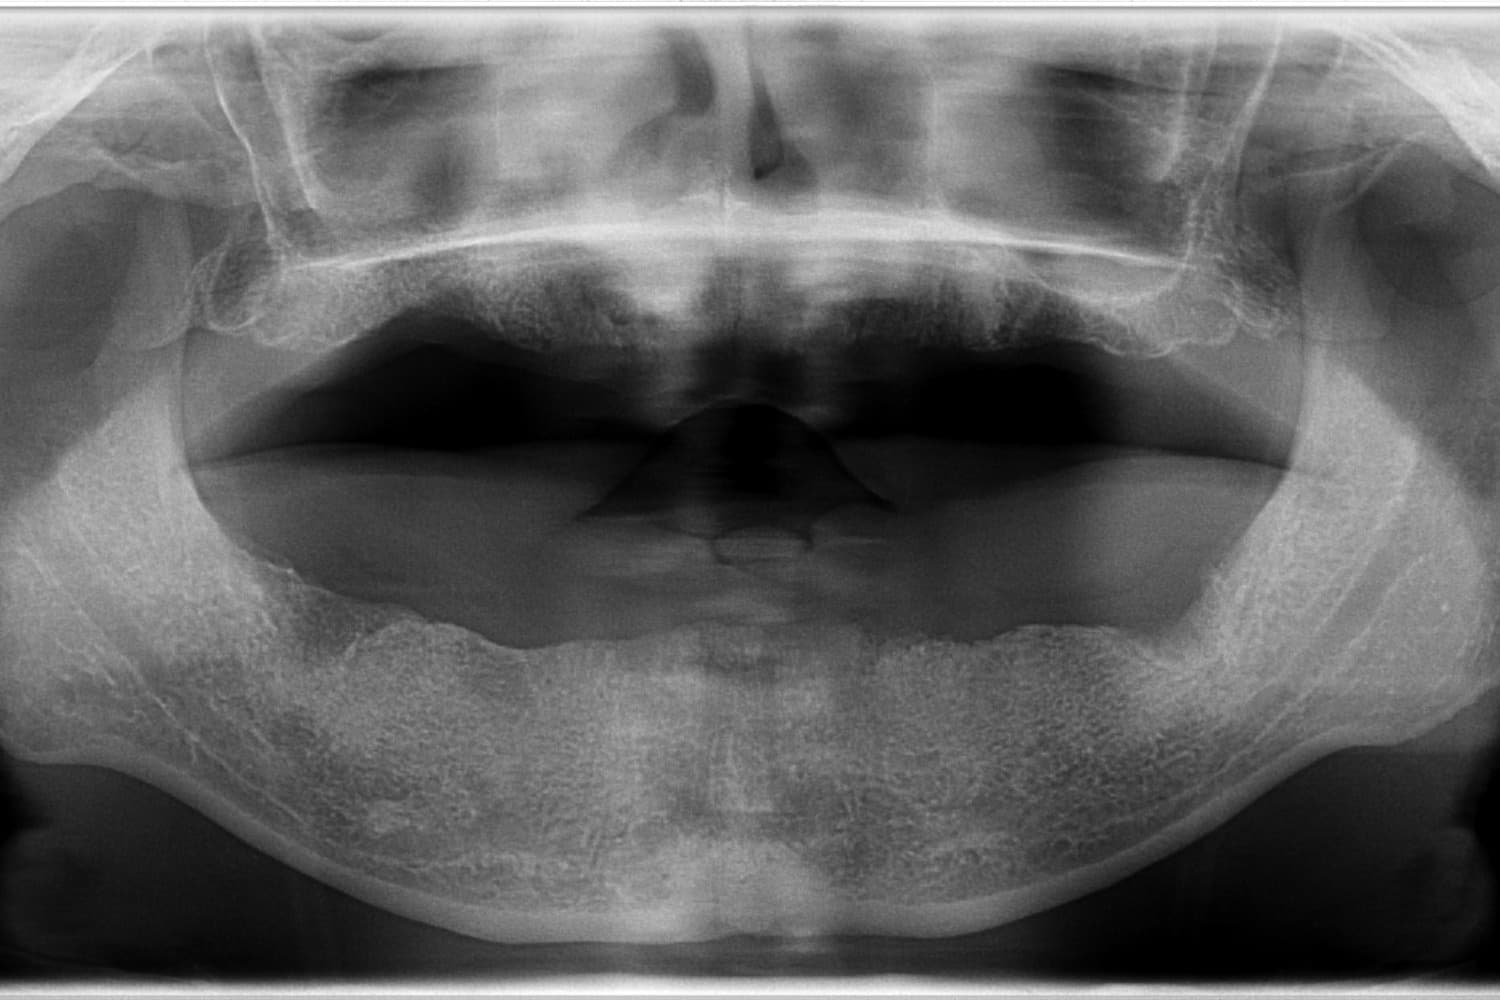

全歯のインプラント治療(50代/男性)

Before

オールオン4

年齢

50代

性別

男性

主訴

他院で総義歯を入れたが、噛むと上の義歯が落ちて使えない。インプラント相談希望。

治療期間

10カ月

治療回数

12回

費用

6,000,000円+骨造成代

副作用・リスク

メインテナンスが出来ていないとインプラント周囲炎になる。よく噛めるため、上部構造が使用していくうちに破損することがある。